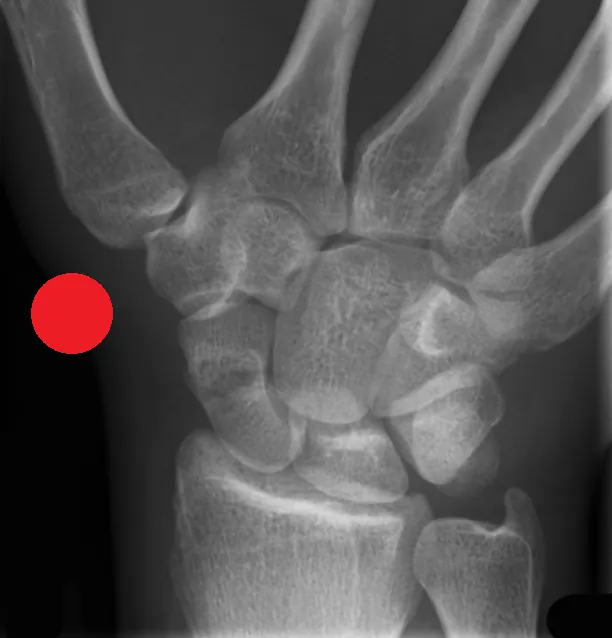

Red Dot X-Ray Interpretation Course (Online)

This Red Dot X-Ray Interpretation Course is designed for Current Advanced Practice Practitioners including Advanced Nurse Practitioners and Advanced Physiotherapist Practitioners working in acute MSK care, for example in A/E or minor injuries and who are seeking to enhance confidence and improve their diagnostic assessment and accuracy. The course focuses on the identification and escalation of suspected pathology, fractures, or other deviations from normal imaging appearances. Participants will build robust knowledge and improve their ability to flag potentially critical findings.

The course focuses on improving the skills needed to identify a range of acute pathologies on x-rays, including fractures, dislocations, chest abnormalities and more. The course will improve patient safety by reducing missed urgent findings, especially whilst waiting for report completion.

• Improved identification of key radiographic features of common acute pathologies, eg. fractures, dislocations, pneumothorax.

• Improved ability to distinguish between normal anatomical variants and common pathological findings on Radiographs.